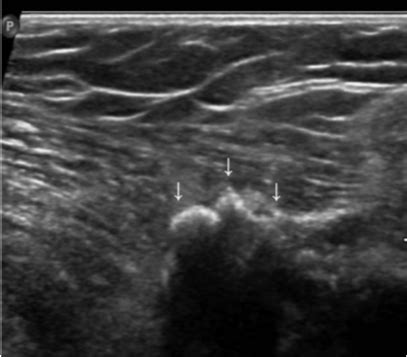

腋窝有结节是怎么回事

腋窝下好多小结节,是正常的淋巴结,大多数是良性,如果不伴疼痛一般没什么问题,观察就可以。

康复指导:建议平时注意饮食要清淡,不要吃过于刺激辛辣容易上火的食物,建议多喝水,多注意休息。